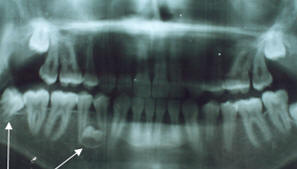

A) Panorámica.- La

12, se observa calcificación de los cuatro terceros molares. (Fig.

3, 4)

Fig.

3.- Radiografía panorámica del paciente de 9 años de

edad, previo al inicio del tratamiento. |